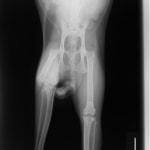

症例3:キルシュナーワイヤーのピンニングによる整復

ペルシャ猫 11ヶ月齢 雄

他院にて左大腿骨遠位の成長板骨折(salter-harrisⅠ型)が認められており、治療相談を目的として来院。当院にて、キルシュナーワイヤーを用いたピンニングにより骨折部位の整復を行いました。術後の経過は良好で、現在も経過観察中です。

術後レントゲン